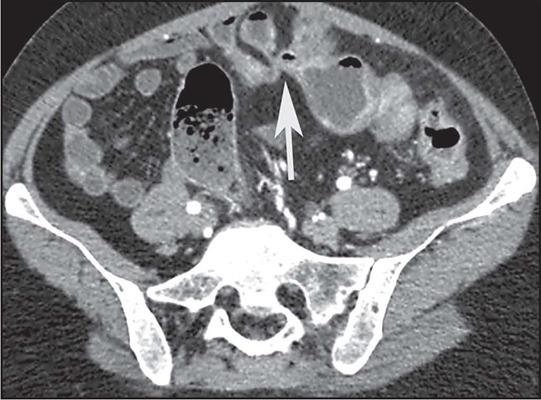

Crohn's disease is an inflammatory bowel disease that can affect any segment of the gastrointestinal tract. It has a variable clinical course, with alternating periods of disease activity and remission. Because the incidence and prevalence of Crohn's disease have been increasing, evaluation by imaging methods has become more important. The most widely used methods are computed tomography enterography, magnetic resonance enterography (as an elective examination), and contrast-enhanced computed tomography (in the context of emergency). Computed tomography enterography and magnetic resonance enterography are useful for diagnosis, follow-up, evaluation of complications, and prognosis. Both can be used in order to evaluate the small bowel loops and the associated mesenteric findings, as well as to evaluate other abdominal organs. They both also can detect signs of disease activity, fibrosis, penetrating disease, and complications. The interpretation of such changes is essential to the multidisciplinary approach, as is the standardization of the nomenclature employed in the reports. In this paper, we review and illustrate the imaging findings of Crohn's disease, using the standardized nomenclature proposed in the multidisciplinary consensus statement issued by the Society of Abdominal Radiology, the Society of Pediatric Radiology, and the American Gastroenterology Association, with recommendations for descriptions, interpretations, and impressions related to those findings.

克罗恩病是一种炎症性肠病,可累及胃肠道的任何节段。其临床病程多变,疾病活动期和缓解期交替出现。由于克罗恩病的发病率和患病率一直在上升,通过影像学方法进行评估变得更加重要。最常用的方法是计算机断层扫描小肠造影、磁共振小肠造影(作为选择性检查)和增强计算机断层扫描(在急诊情况下)。计算机断层扫描小肠造影和磁共振小肠造影对诊断、随访、并发症评估及预后判断均有帮助。两者均可用于评估小肠肠袢及相关肠系膜表现,以及评估其他腹部器官。它们还都能检测疾病活动、纤维化、穿透性病变及并发症的征象。对这些改变的解读对于多学科诊疗方法至关重要,报告中使用的命名标准化也同样重要。在本文中,我们使用腹部放射学会、儿科放射学会和美国胃肠病学会发布的多学科共识声明中提出的标准化命名,回顾并阐述克罗恩病的影像学表现,并对与这些表现相关的描述、解读及印象给出建议。